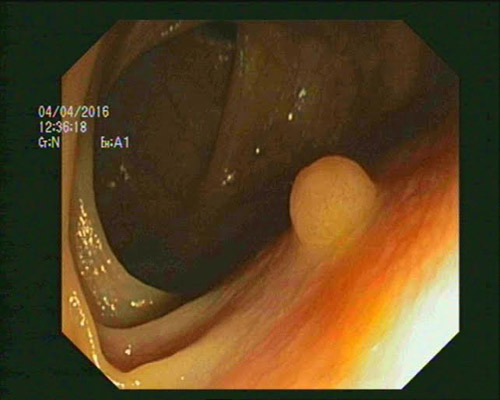

Do phát hiện ung thư đại tràng ở giai đoạn I, anh Hải đã được bác sĩ Vinmec phẫu thuật thành công. |